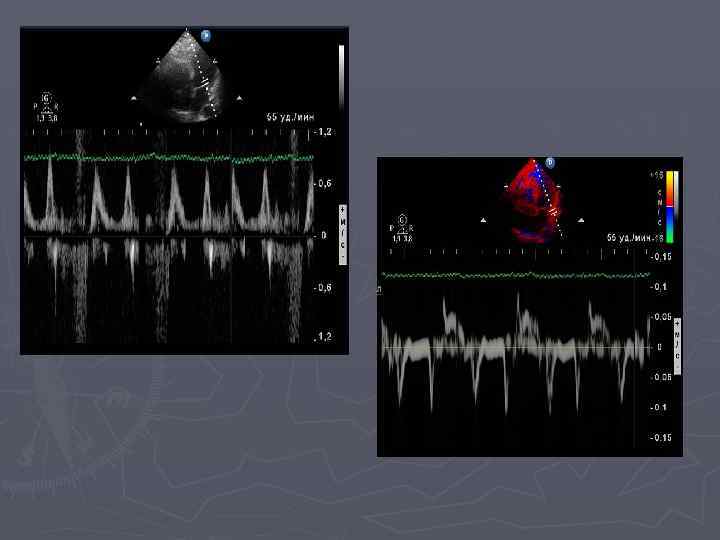

Оценка диастолической функции по данным тканевого допплеровского исследования ► ► ► ► Расчет на уровне фиброзных колец МК и ТК: IVRTm-время изоволюмичесского миокардиального расслабления(мс) IVCT m- время изоволюмического миокардиального сокращения (мс) DTe m-время замедления волны Е раннего диастолического движения (мс) Em-скорость раннего диастолического движени (см/с) Am-скорость позднего диастолического движения (см/с) Em/Am-отношение скорости раннего и позднего диастолического движения фиброзного кольца ETm-время от начала раннего диастолического движения до конца позднего диастолического движения или продолжительность диастолы (мс)

Маркер глобальной сократимости. Миокардиальный индекс (Tei-индекс) рассчитывался по трансмитральному потоку, как сумма периодов изоволюмического сокращения и изоволюмического расслабления , отнесенная ко времени изгнания Тei=(а-в)/в ► Модифицированный индекс Тei (Tei-ТД) рассчитывался при оценке спектра тканевого допплера от фиброзного кольца МК по боковой стенке Tei-ТД= (а´-в´)/в´ ► В норме Тei-индекс менее 0, 40 Tei-ТД 0, 33± 0, 05 ►